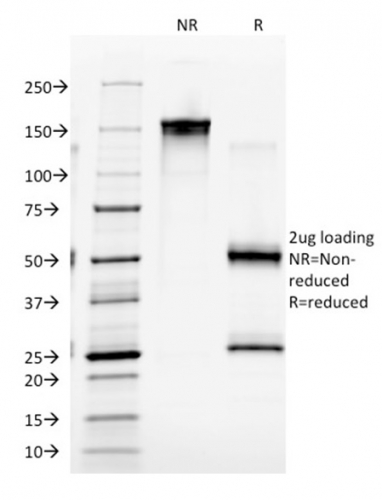

SDS-PAGE Analysis Purified EGFR Mouse Monoclonal Antibody (GFR/2341). Confirmation of Integrity and Purity of Antibody.

This MAb recognizes a protein of 170kDa, identified as EGFR. EGFR is type I receptor tyrosine kinase with sequence homology to erbB-1, -2, -3 -4 or HER-1, -2, -3 -4. It binds to Epidermal Growth Factor (EGF), Transforming Growth Factor-a (TGF-a), Heparin-binding EGF (HB-EGF), amphiregulin, betacellulin and epiregulin. EGFR is overexpressed in tumors of breast, brain, bladder, lung, gastric, head & neck, esophagus, cervix, vulva, ovary, and endometrium. It is predominantly present in squamous cell carcinomas.